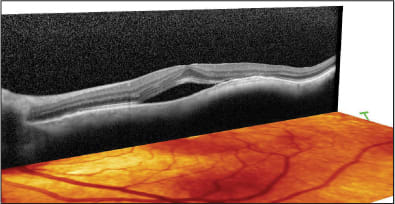

Figures 1 and 2. Bilateral Z syndrome in high myope with gap between implant and posterior capsule. Note severe fibrosis of haptics.

The patient assured me that he saw perfectly out of the left eye as recently as a year ago. I decided to attempt an OCT evaluation, which revealed a lamellar macular hole in the right eye and a severe vitreomacular traction syndrome in the left eye (Figures 7 and 8). The patient was referred for vitreo-retinal surgery in the left eye, which was performed successfully, and cataract surgery followed in both eyes, leading to 20/30 vision in the OD and 20/50 in the OS.